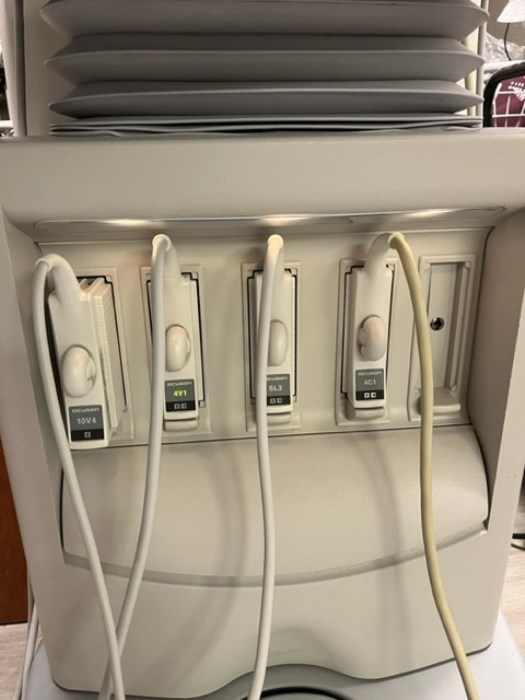

Probes: 15L8w, 4V1, 10V4, 6L3, 4C1